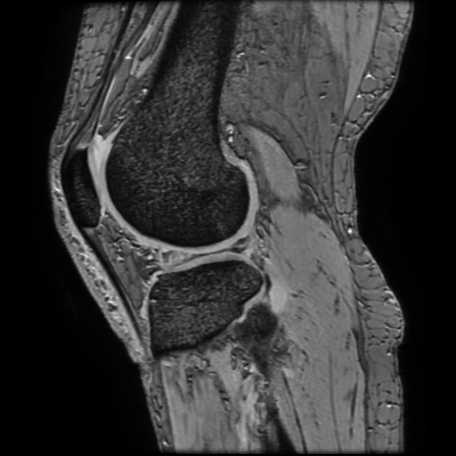

膝関節

半月板損傷